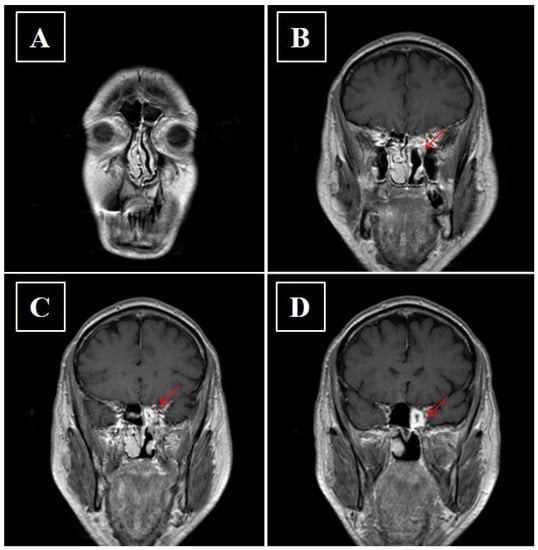

- Kawaguchi, M.; Kato, H.; Tomita, H.; Mizuta, K.; Aoki, M.; Hara, A.; Matsuo, M. Imaging Characteristics of Malignant Sinonasal Tumors. J. Clin. Med. 2017, 6, 116. [Google Scholar] [CrossRef]